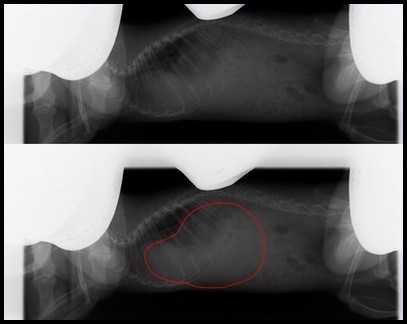

Il n'y a pas grand chose à faire, si ce n'est surveiller vos rats et agir au moindre doute. Des radios des poumons peuvent être effectuées en contrôle, les abcès y apparaissent comme des masses noires et trahissent la présence et l'activation de la maladie.

Ces photos peuvent être transmises à votre vétérinaire, afin de l'aider dans son diagnostic. Un abcès dans les poumons n'est pas toujours synonyme de corynébactéries actives, mais il convient de conserver ce détail en mémoire pour recouper les informations par la suite.

Radio de cette rate, où on peut voir la masse